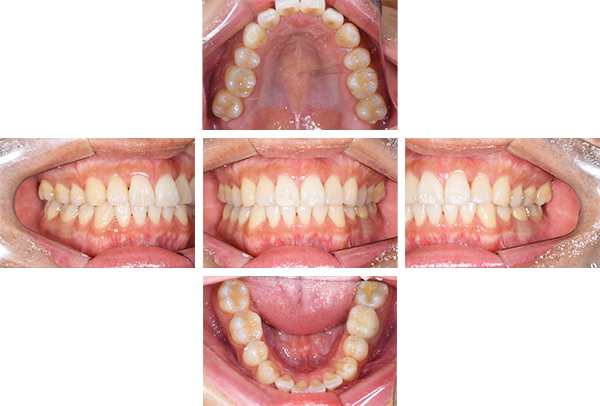

歯列矯正・インレー・クラウン症例

前歯が黒っぽいのが気になる、

悪いところは全部治したい

年齢 54代女性

主訴 歯をきれいにしたい

治療

期間

4年

費用 セラミックインレー 12本

660,000円

オールセラミックプレミアムクラウン 3本

495,000円

矯正 874,900円

計 2,029,900円(税込)

症例写真(治療前)

治療前:

八重歯が目立ちます。また銀歯もおおく、見た目が気になります。虫歯も散見できます。

症例写真(治療後)

担当医師所見

治療後:

矯正治療と虫歯の治療すべて終わったときの写真になります。見た目も最初の頃とは全く違いますし、お口の中もすごく綺麗です。

方針

まずは虫歯の治療を行い、被せ物をする部分は仮歯をいれて矯正を行う。矯正終了後、仮歯の部分を最終的な被せ物に変えていく。また気になっていた銀歯もセラミックに変えて終了となった。

内容

セラミックインレー、オールセラミックプレミアム、矯正